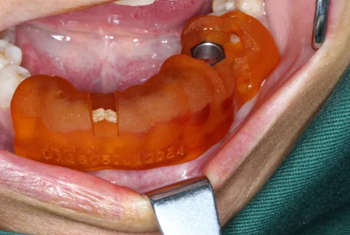

1.碘伏浸泡消毒后的導(dǎo)板在患者口內(nèi)試戴,就位準確、十分穩(wěn)固。

2.使用牙齦環(huán)切刀施行不翻瓣手術(shù),創(chuàng)傷小,保護患者牙齦軟組織形態(tài)。